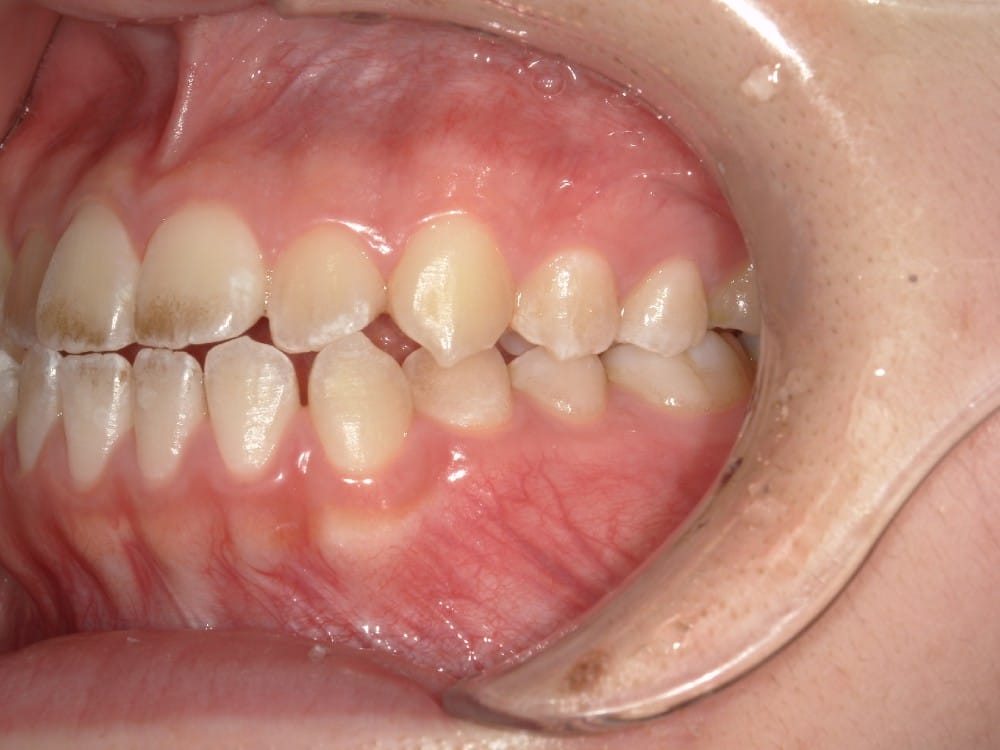

30代の女性で、受け口とガタガタを主訴にご来院されました。

治療前

分析しますと

- 骨格的な上下あごの前後差は中等度〜重度

- 噛み合わせの位置も下あごの奥歯が半分くらい前にズレていた

- 上の前歯が内側に傾斜している

というケースで、外科的な処置も検討するようなケースでした。

骨格的なズレや奥歯の噛み合わせのズレもあり、重度の受け口でしたが、上あごの前歯が内側に傾斜しているため、本来の歯の軸に戻すことで、受け口を改善できると診断し、治療を開始しました。

先ほどのケースと同じように、患者さまに外科的な手術の選択肢も提示しましたが、希望されず、横顔の変化はおそらく起こらないことを納得の上、治療をスタートいたしました。

今回のケースも奥歯の移動量が大きいため、マウスピースだけでは難しいと判断し、カリエールとよばれる装置を補助的に使用し、上下の噛み合わせの前後関係を整えることで、手術を行わずに機能面と見た目の両方が改善することにしました。

治療中の直近の写真です。生まれつき小さな歯である前から両側の2番目の歯は、被せ物をして見た目の回復をする予定にしています。